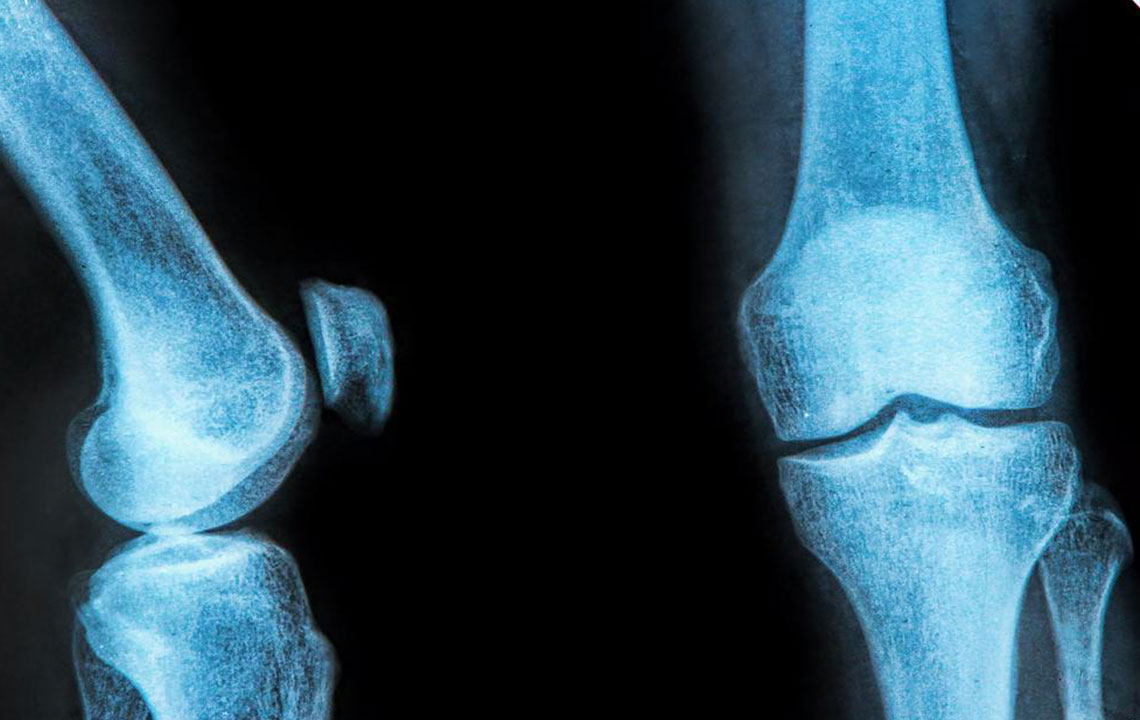

The rubbery C-shaped disc cushioning your knee is a meniscus. There are two menisci in each knee. One at the inner side and the other on the outer side. It is this meniscus that helps to keep your knee steady. It balances your body weight around your knee. If there is a tear in the meniscus, you will experience a lot of pain. It will also prevent the proper functioning of your knee. This kind of a painful injury to the knee is called meniscus tear. It can damage your knee permanently. A brace for meniscus tear can ease your pain.